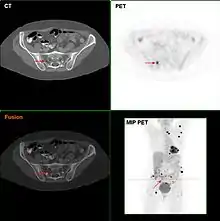

Metastatic melanomas can be detected by X-rays, CT scans, MRIs, PET and PET/CTs, ultrasound, LDH testing and photoacoustic detection.[90] However, there is lack of evidence in the accuracy of staging of people with melanoma with various imaging methods.[91]

F18-FDG PET/CT in a melanoma patient showing multiple lesions, most likely metastases